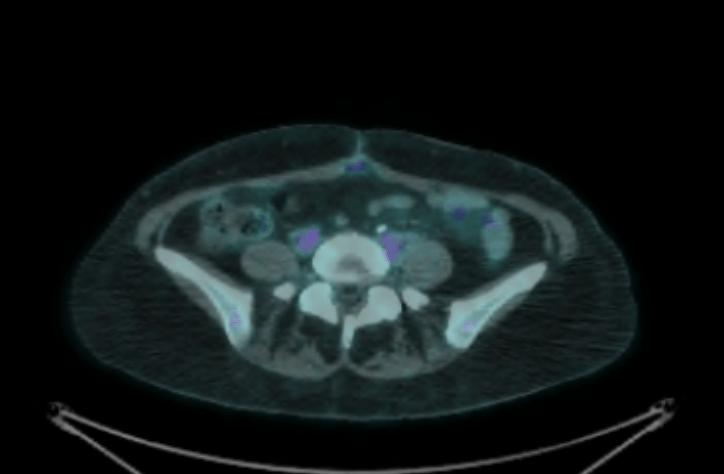

I've had 3 scans. First scan it was 3cm with a SUV max score of 5 point something. (For my type of cancer, 2.5 or above is considered cancerous... it's how much of the radioactive stuff is detected in the spot. Or something like that.) My second scan it was about 1 cm with a SUV max score of I think 2.6. Then this last scan it was still 1 cm but the SUV max score was 1.9. I'd have to log back in to confirm those numbers but that's what I recall.

February: 3 cm:

June: 1 cm with inflammation at the staple line of my Hartmann's pouch:

September: Inflammation resolved, spot still 1 cm (but no FDG uptake):

Previously depicted left retroperitoneal nodal mass in the common iliac station measures 0.9 cm in short axis, unchanged (SUV max 1.9, previously 2.6, image 224). Elsewhere below the diaphragm, tracer activity is unremarkable. Calcified mass closely associated with bowel in the left hemiabdomen is unchanged. Left renal cyst. There are postoperative changes of the colon with left lower quadrant ostomy. There are no FDG avid skeletal lesions.

No findings convincing for FDG avid malignancy. The left common iliac nodal lesion is not FDG avid and is similar in size to the prior study.